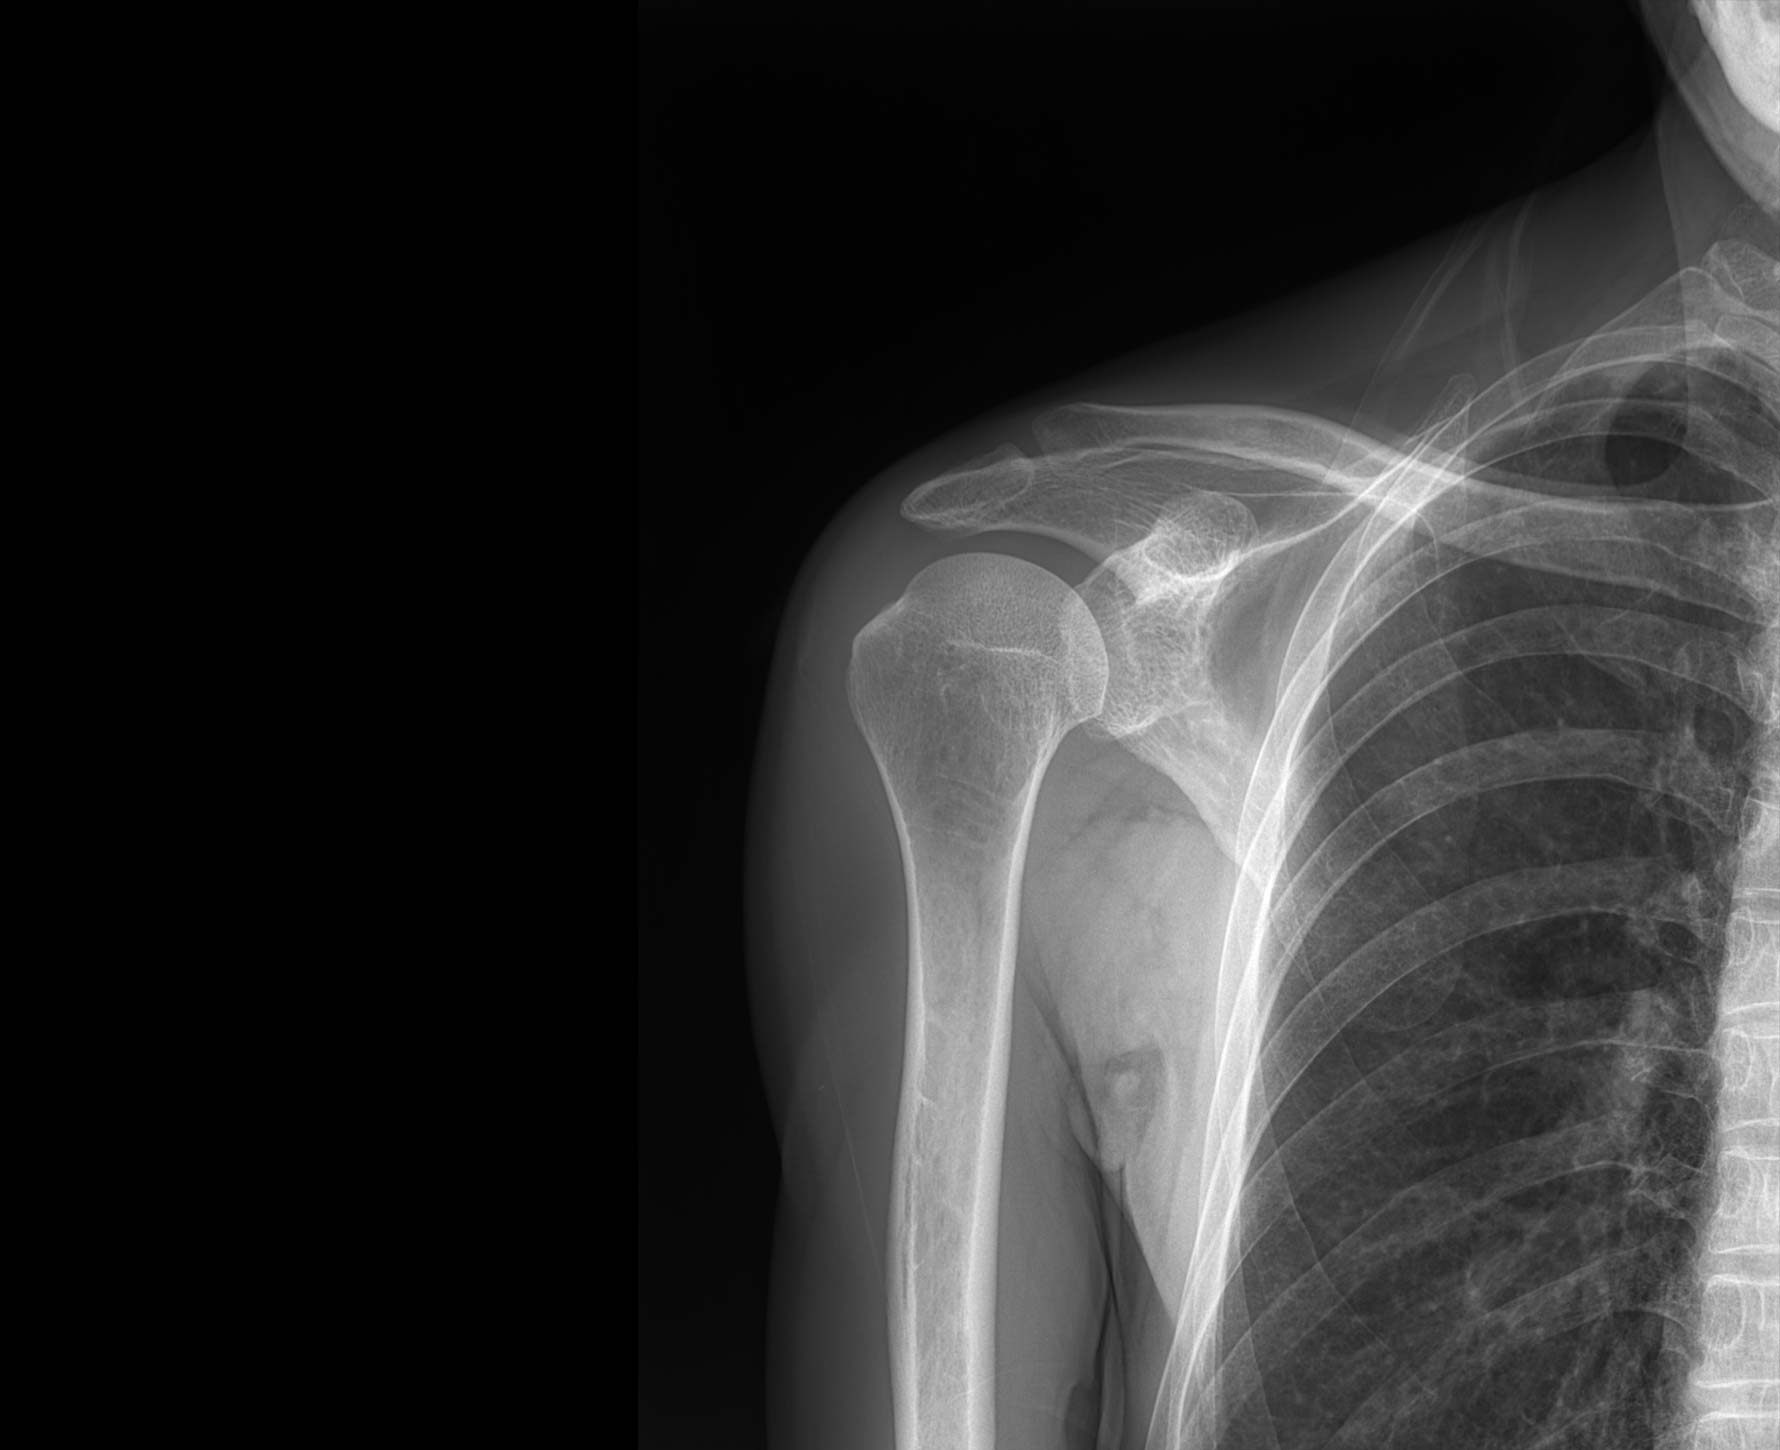

适用于全身各部位摄影

(常规摄影和特殊摄影)

适用于全身各部位摄影

(常规摄影和特殊摄影)